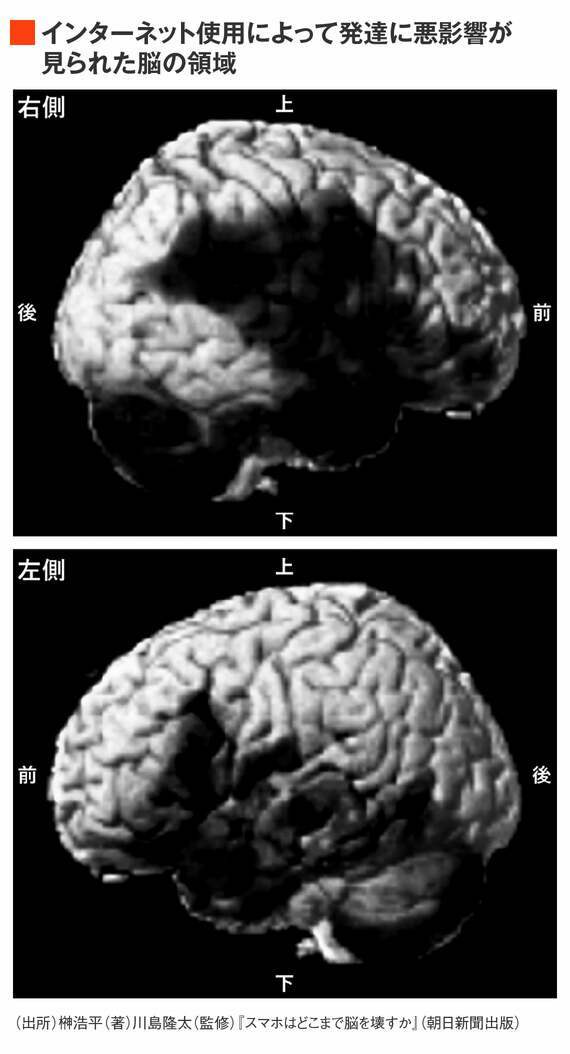

東北大学加齢医学研究所では、約5〜18歳の子どもたち223名の脳をMRIで計測し、3年間の脳の発達とインターネット使用習慣との関係を調べました。

アンケート調査により子どもたちのインターネット使用習慣を尋ね、同時に言語能力に関する知能検査を行いました。そして、脳の発達を調べるために、MRIを用いて子どもたちの脳の容積を計測しました。3年後に同じ計測を行った結果、インターネットを頻繁に使っていた子どもたちほど、3年間の言語能力の発達が小さく、幅広い範囲における脳の発達にも悪影響が見られました。

下の画像の黒い部分が、発達に悪影響が見られた脳の領域を表しています。前頭前野をはじめ、記憶や学習に関わる海馬、言葉や感情に関係する領域などが含まれています。どれも私たちが生きるうえで必要となる大切な機能です。特に衝撃を受けたのは、インターネットを「ほぼ毎日使用する」と回答した子どもたちの脳の発達は、ほとんどゼロに近い数値となっていたことです。

つまり、インターネットを毎日使っている子どもたちは、3年間で脳がまったく発達していなかったのです。脳の広範囲で発達が止まってしまっているわけですから、スマホを使った分だけたくさん勉強をすれば悪影響を補って帳消しにできる、とはいかないのです。